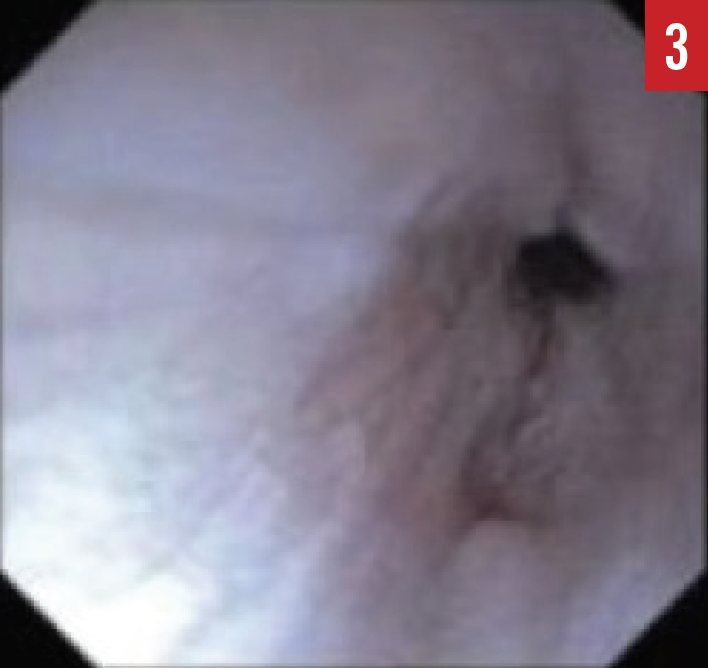

When the presence of EoE is suspected, esophagogastroduodenoscopy (EGD) must be performed by a pediatric gastroenterologist. During the EGD, biopsies are taken from various areas of the esophagus, stomach, and duodenum. A number of endoscopic features are common in patients with EoE, including esophageal edema, rings or strictures, esophageal furrowing, or white exudates (Figures 1-3).

Figure 3. An EGD image of an esophageal stricture.